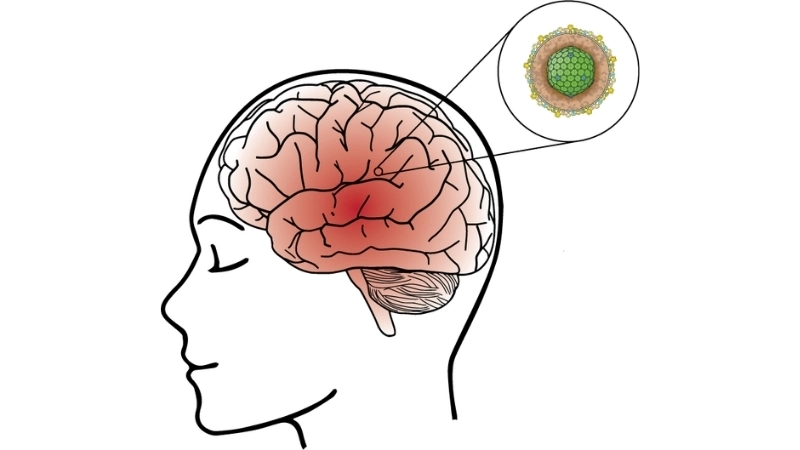

Image description of Viral Encephalitis

Viral encephalitis is a serious condition where a viral infection causes inflammation in the brain. It can range from mild to life-threatening, requiring early detection and treatment.